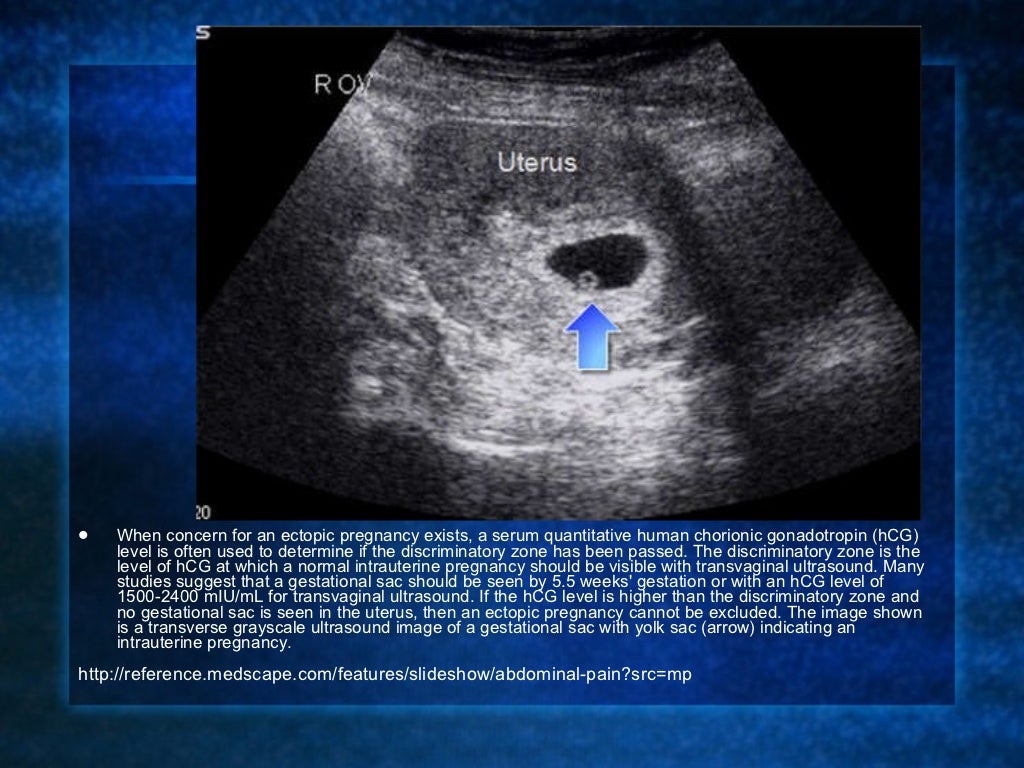

На узи определить внематочную беременность 115 фотографий